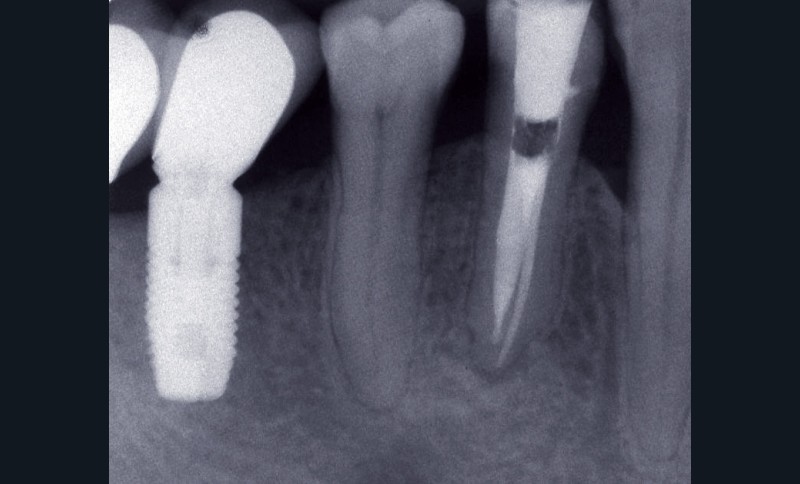

– obtention d’une étanchéité coronaire efficace le plus rapidement possible par le scellement d’un inlay-core et d’une couronne provisoire si les tissus dentaires résiduels sont insuffisants (fig. 1).

L’étanchéité des obturations coronaires provisoires et permanentes conditionne pour une grande part la réussite du traitement endodontique. Ainsi, en 1987, Swanson et Madison [42] ont montré qu’un traitement endodontique parfaitement réalisé était infiltré par des bactéries sur près de 85 % de sa hauteur entre 3 et 56 jours en l’absence de fermeture de la cavité d’accès endodontique. De la même manière, Torabinejad et coll. [44] ont étudié la pénétration de deux espèces bactériennes (Staphylococcus epidermis et Proteus vulgaris) au sein de canaux obturés par une technique de condensation latérale. Ils ont montré que dans plus de 50 % des canaux traités, les bactéries étaient retrouvées au niveau de l’apex 19 jours seulement après exposition à Staphylococcus epidermis et 42 jours après exposition de la cavité d’accès à Proteus vulgaris. Khayat et coll., en 1993 [12], ont montré qu’après 30 jours d’exposition à la salive naturelle, des bactéries étaient retrouvées au niveau apical pour l’ensemble des canaux traités.

En 1995, Ray et Trope [22] ont évalué radiographiquement sur près de 1 000 dents l’apparition ou non de lésions apicales selon les qualités de la restauration coronaire et de l’obturation canalaire. Les auteurs ont montré qu’un traitement endodontique de mauvaise qualité associé à une restauration coronaire de qualité donne de meilleurs résultats en termes de non-survenue d’une LIPOE qu’un traitement endodontique bien mené associé à une obturation coronaire défectueuse. Tavares et coll., en 2009 [43], confirment cette étude, en montrant que le taux de succès du traitement endodontique est plus élevé lorsque la restauration coronaire est de bonne qualité, et ce, indépendamment de la qualité du traitement endodontique.

Toutefois, la qualité d’une obturation coronaire, aussi bonne soit-elle, ne peut en aucun cas compenser un traitement endodontique de mauvaise qualité [45].